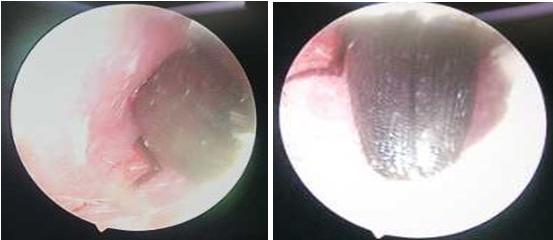

考慮到昆蟲是活體時進(jìn)入耳道內(nèi)的,有倒鉤的腿部或者口器可能已經(jīng)對耳道及鼓膜造成了損傷。同時,孩子耳道內(nèi)已經(jīng)腫脹,因為疼痛恐懼極不配合治療。耳鼻喉科團(tuán)隊緊急討論決定,利用耳內(nèi)窺鏡手術(shù)取出。

經(jīng)過緊急術(shù)前準(zhǔn)備,當(dāng)天,耳鼻喉科團(tuán)隊通過耳內(nèi)窺鏡從小麗耳朵里取出一只1.5厘米長完整硬殼昆蟲!